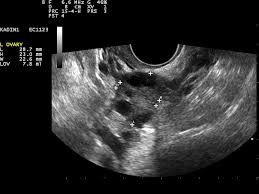

Die Ultraschalluntersuchung Sonografie ist meist die erste bildgebende Untersuchung bei Verdacht auf Blasenkrebs. Die Klassifikation Stadieneinteilung oder Staging genannt ist ein wichtiger Baustein für die Wahl der optimalen Therapie. Dabei kann der Arzt Blase Nieren und Harnwege begutachten.

Ultraschall Der Harnblase

Eine Ultraschalluntersuchung ermöglicht auch Blasensteine oder einen Blasentumor zu entdecken. Wirken Lymphknoten verdächtig veranlassen Ärzte in der Regel eine Biopsie oder Lymphknotenentnahme. Per Ultraschall lassen sich auch mögliche andere Ursachen für Beschwerden erkennen beispielsweise Nieren- Blasen-. Blasenkrebs kann als Folge einer Strahlentherapie entstehen. Blasenkrebs Mit der Diagnose Blasenkrebs hat der Patient nicht gerechnet. Sofern der Verdacht auf Blasenkrebs besteht nimmt der Arzt eine gründliche Untersuchung vor. Sie stellt zusammen mit der Biopsie Gewebeprobeentnahme die wichtigste Untersuchung für die Diagnose von Blasenkrebs dar. Ziel der Diagnostik ist eine möglichst frühzeitige Diagnosestellung und die Erhärtung oder Ausräumung des Verdachts auf Blasenkrebs. So stellen Ärzte beispielsweise bei Patienten mit einem Gebärmuttertumor ein erhöhtes Risiko für.

Die wichtigste Untersuchung zur Diagnose-Stellung ist die Spiegelung der Harnblase die sogenannte Zystoskopie. Es gibt keine Tumormarker im Blut die spezifisch für Blasenkrebs sind. Per Tastuntersuchung nimmt er dabei die Nierengegend den Unterbauch und die Geschlechtsorgane unter die Lupe. Blasenkrebs Mit der Diagnose Blasenkrebs hat der Patient nicht gerechnet. Liegt ein invasiver Harnblasentumor vor sind tiefgreifende Maßnahmen nötig. Wirken Lymphknoten verdächtig veranlassen Ärzte in der Regel eine Biopsie oder Lymphknotenentnahme. Die Ultraschalluntersuchung Sonografie ist meist die erste bildgebende Untersuchung bei Verdacht auf Blasenkrebs.